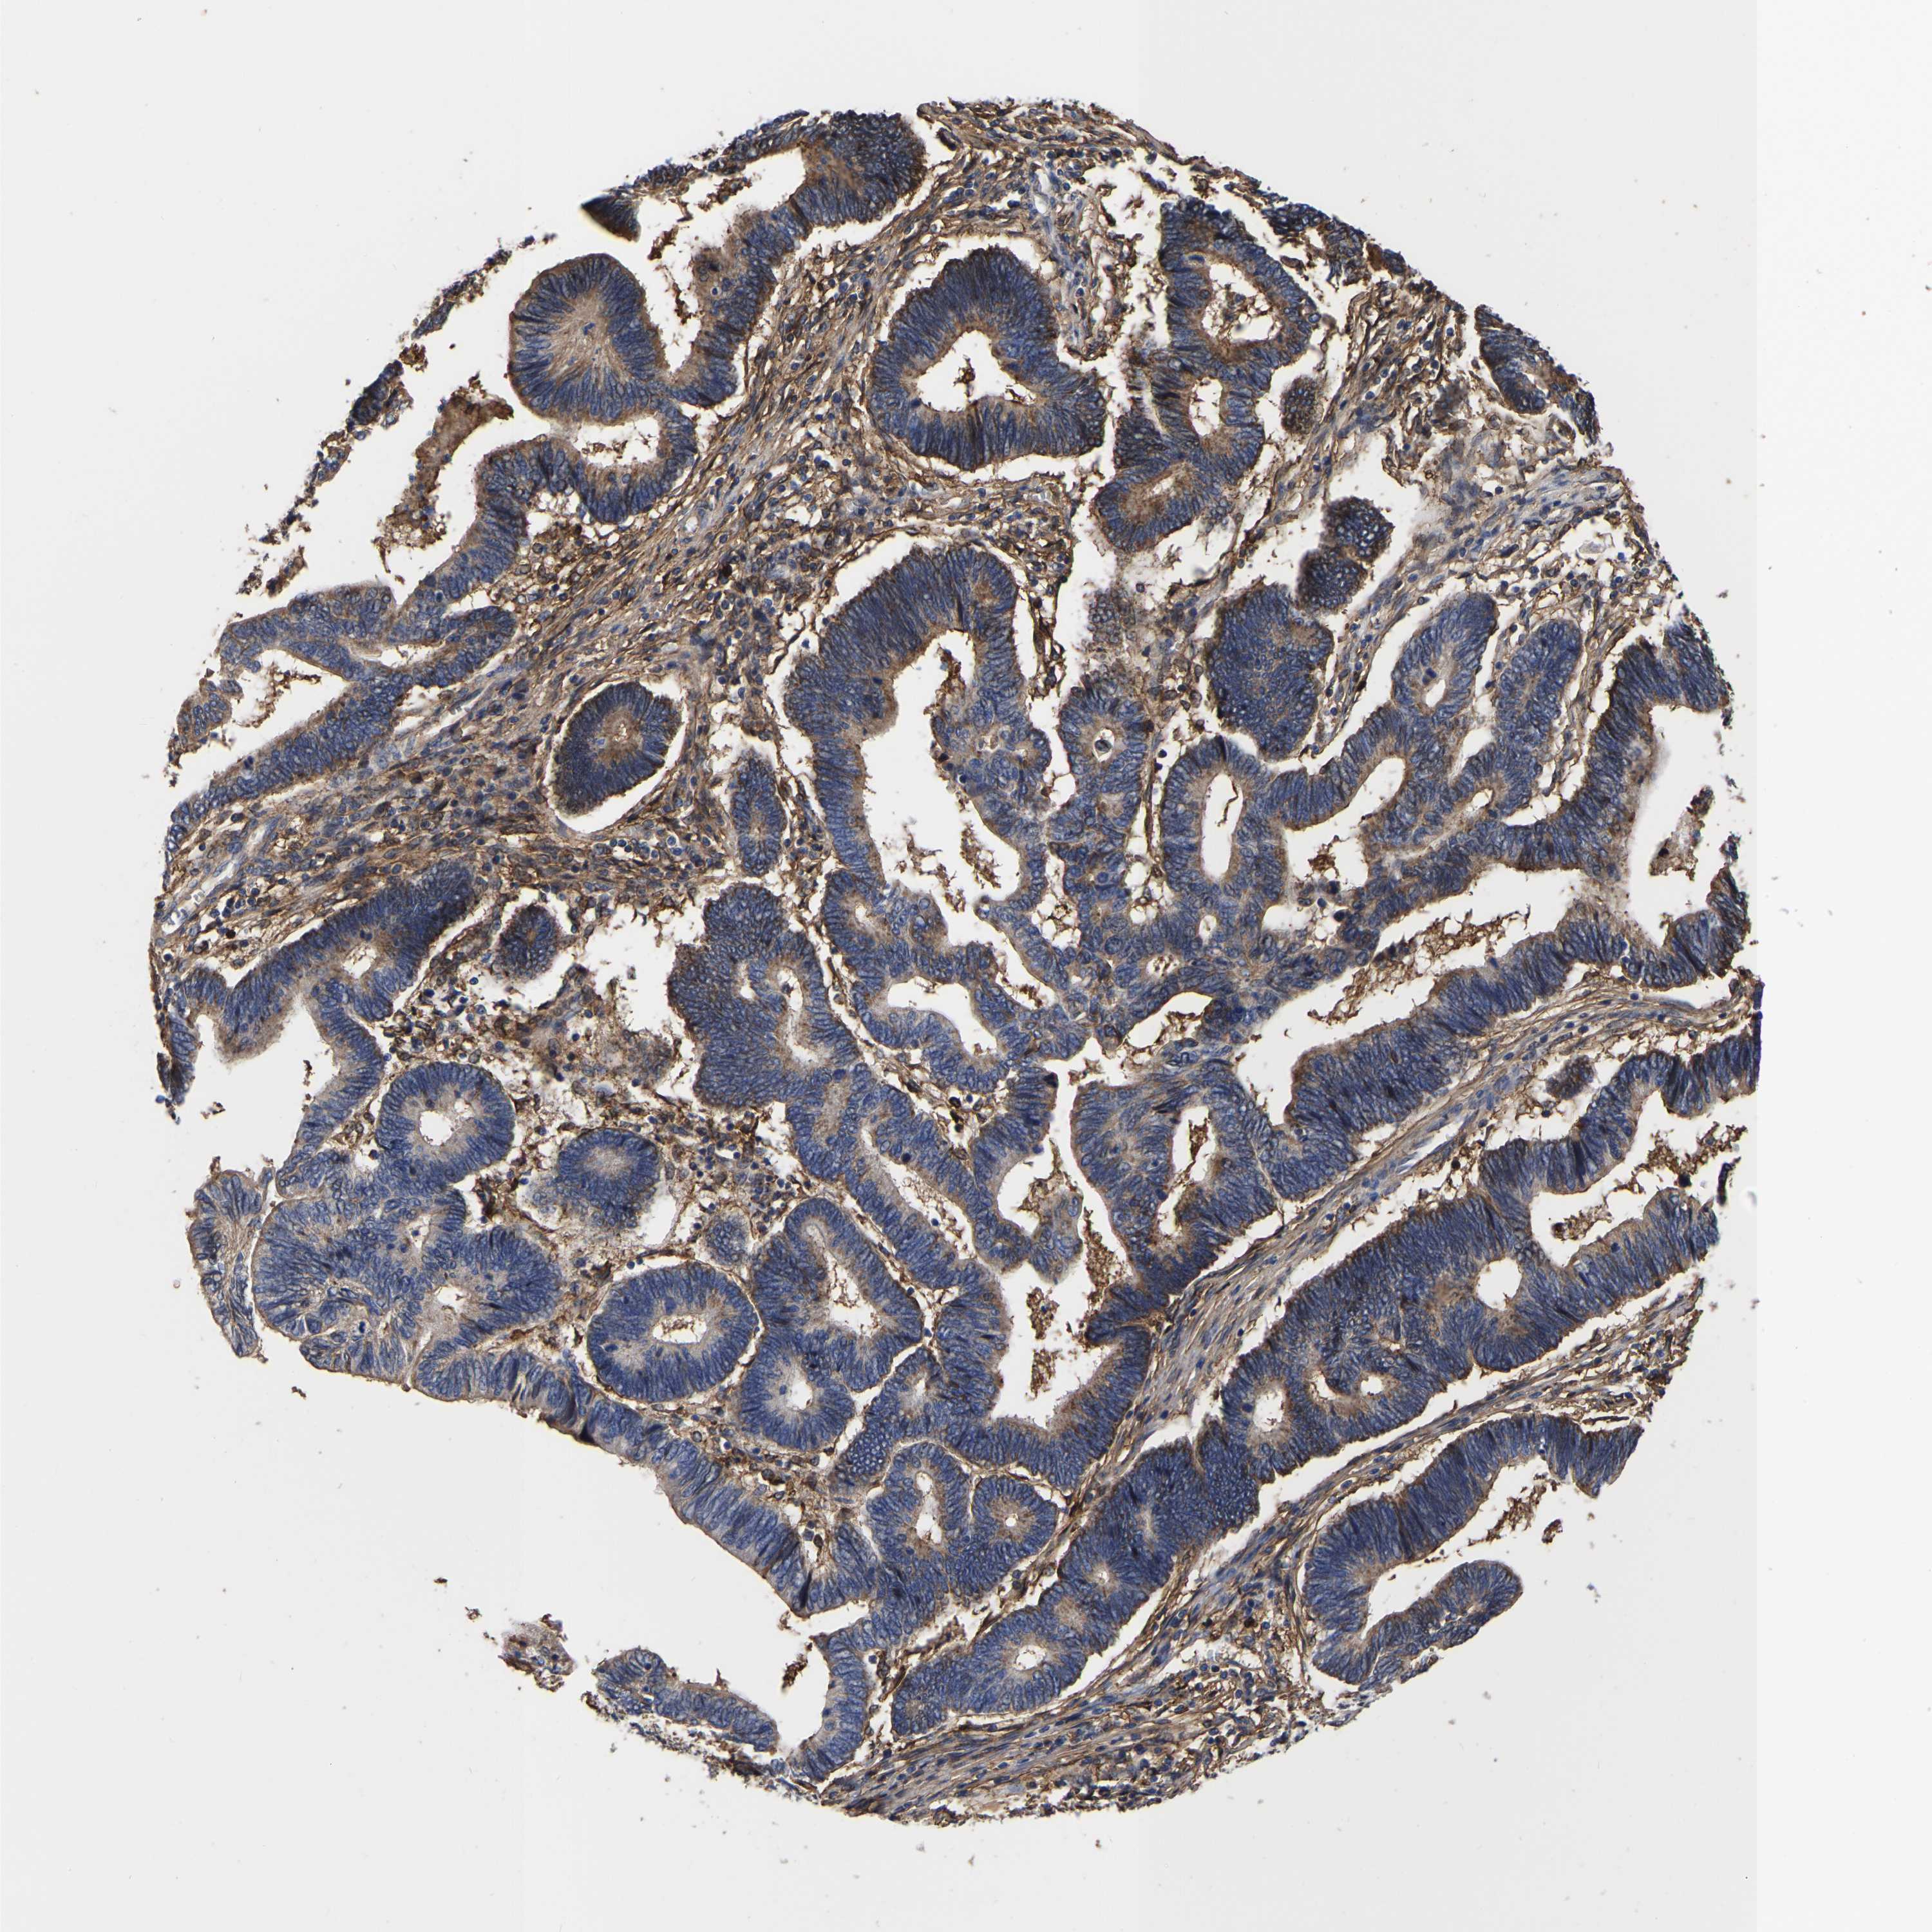

PANCREATIC CANCER - Protein expressioni

A mouse-over function shows sample information and annotation data. Click on an image to view it in a full screen mode. Samples can be filtered based on level of antibody staining by selecting one or several of the following categories: high, medium, low and not detected. The assay and annotation is described here.

Note that samples used for immunohistochemistry by the Human Protein Atlas do not correspond to samples in the TCGA dataset.

Antibody stainingi

Antibody staining in the annotated cell types in the current human tissue is reported as not detected, low, medium, or high, based on conventional immunohistochemistry profiling in selected tissues. This score is based on the combination of the staining intensity and fraction of stained cells.

Each image is clickable and will lead to virtual microscopy that enables deeper exploration of all samples and also displays staining intensity scores, fraction scores and subcellular localization as well as patient and tissue information for each sample.

Antibody HPA018844

Staining

High

Medium

Low

Not detected

Intensity

Strong

Moderate

Weak

Negative

Quantity

>75%

75%-25%

<25%

None

Location

Nuclear

Cytoplasmic/membranous

Cytoplasmic/membranous,nuclear

Adenocarcinoma, NOS